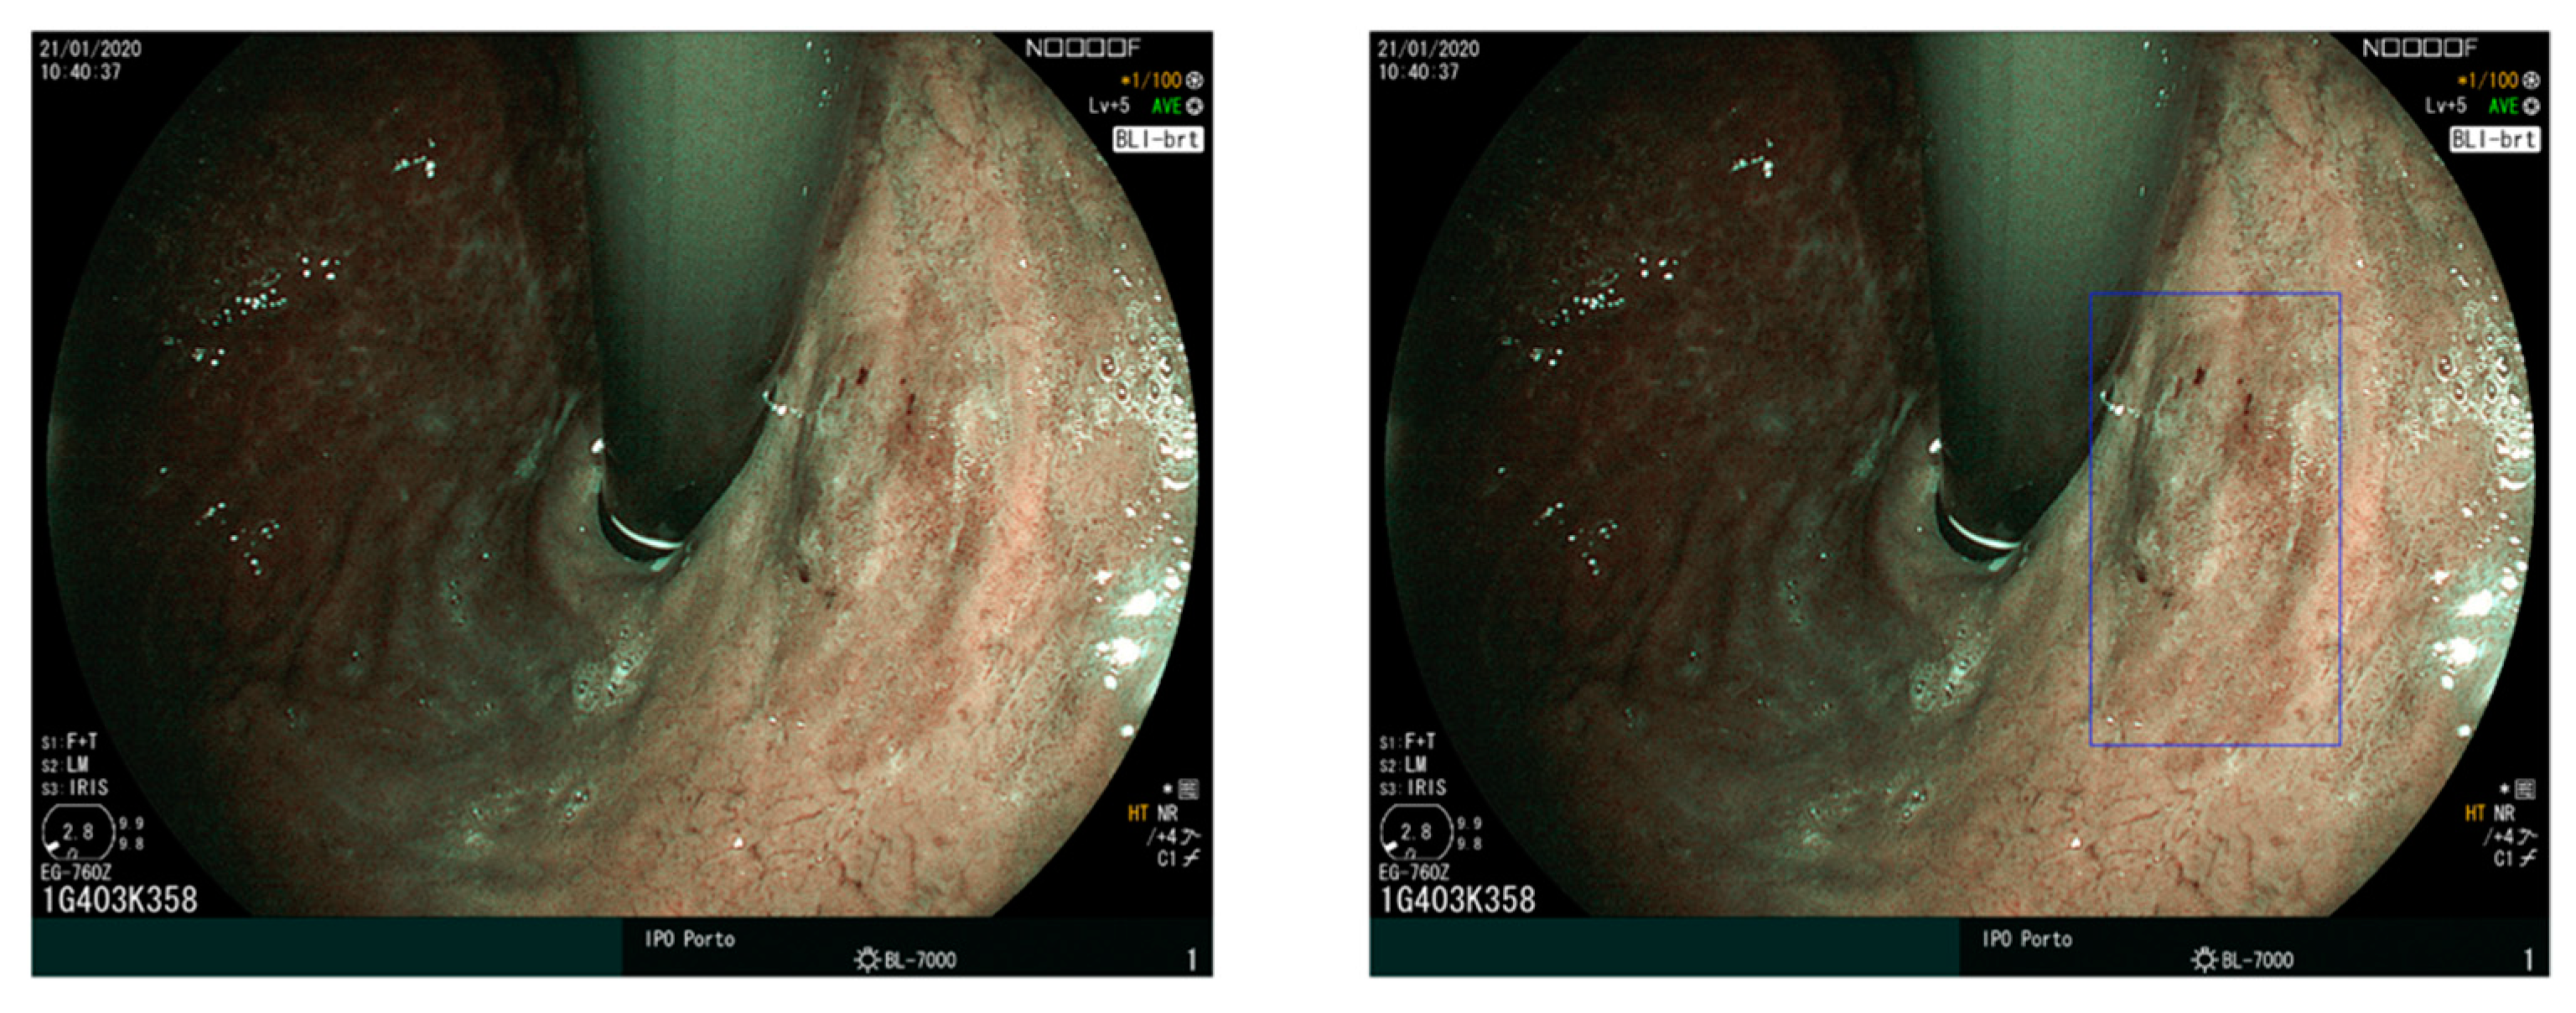

3.2. Lesion Detection in UGIE

The detection of all existing lesions is the goal of UGIE. Since early lesions are often subtle and difficult to detect for human eyes, the exposure of all the mucosa may not suffice to guarantee that every lesion is detected, and AI can also have a role in improving lesion detection. An example is reported in Figure 5, which shows an early gastric cancer lesion missed by an endoscopist and correctly identified by the convolutional neural network algorithm presented in [51,52]. If we distinguish between lesion detection (Are there any lesions in this UGIE exam? If so, where are these lesions?) and lesion characterization (How does each lesion contribute to a diagnostic decision?), and accept that non-visualized lesions are part of the exam quality challenge and not the lesion detection challenge, what is the clinical motivation for this AI challenge? In fact, expert gastroenterologists typically exhibit very good performance in a lesion detection task if the lesion is correctly visualized.

Figure 5.

(Left) An early gastric cancer lesion missed by an endoscopist and (Right) correctly identified by the convolutional neural network by bounding box regression model by [52,53]. Note that, not only is the CNN’s prediction cued from subtle textural changes in the mucosa, but also that the output is a plausible bounding box around it. (Adapted from data kindly provided by Ishioka et al. [52]).